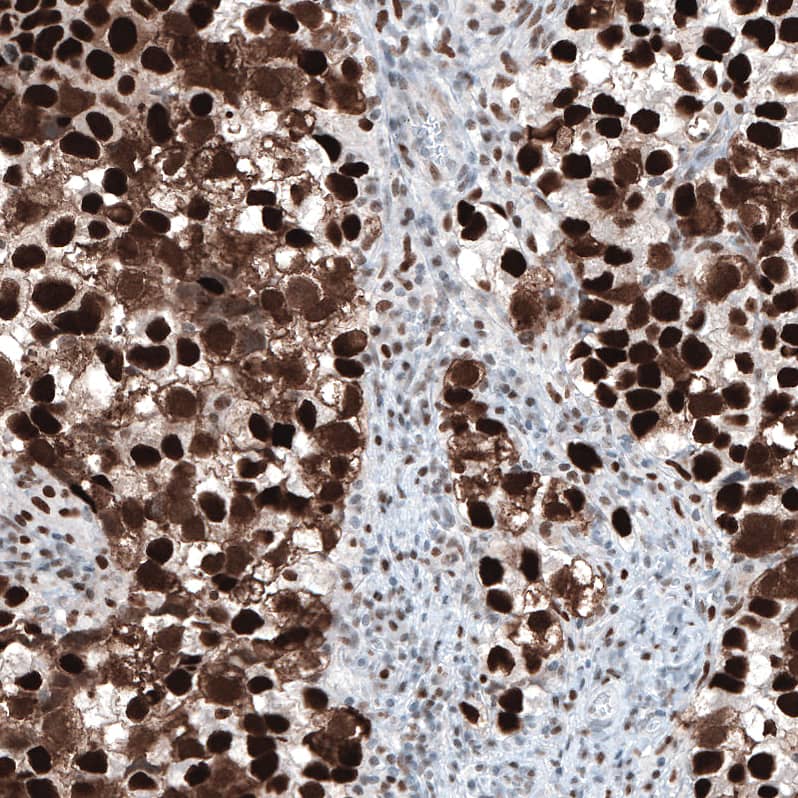

Staining of human embryonal carcinoma of testis shows strong nuclear positivity.

Staining of human testis cancer, seminoma shows strong nuclear positivity.